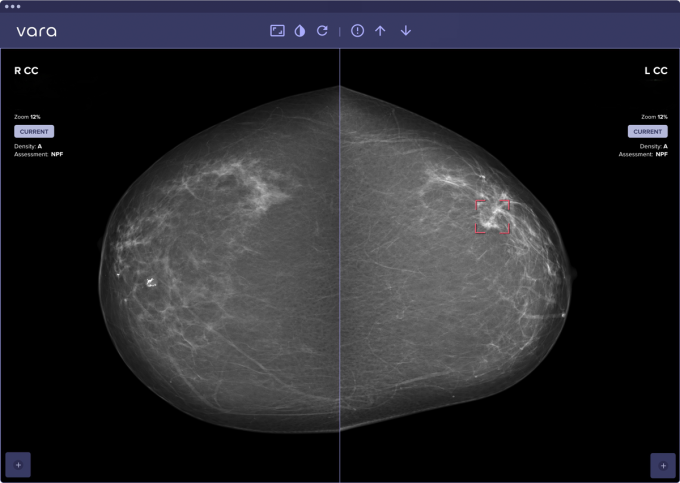

So funktioniert die KI: Unauffällige Mammographie-Bilder werden ausgesondert, während Bereiche, in denen die KI Brustkrebs vermutet, gekennzeichnet werden, sodass die Ärzt:innen dort genauer hinsehen können. Die Fehlerquote der KI ist verschwindend gering. „Sie übersieht nur äußerst selten etwas“, so Dr. Lorenzen. Darüber hinaus ermittelt das Programm einen individuellen Risikowert für jedes Mammographie-Bild. Der Einsatz von KI bei der Beurteilung von Mammographie-Aufnahmen wird in der Regel von privaten Krankenkassen übernommen, während gesetzliche Krankenkassen diese Zusatzleistung bislang nicht erstatten.